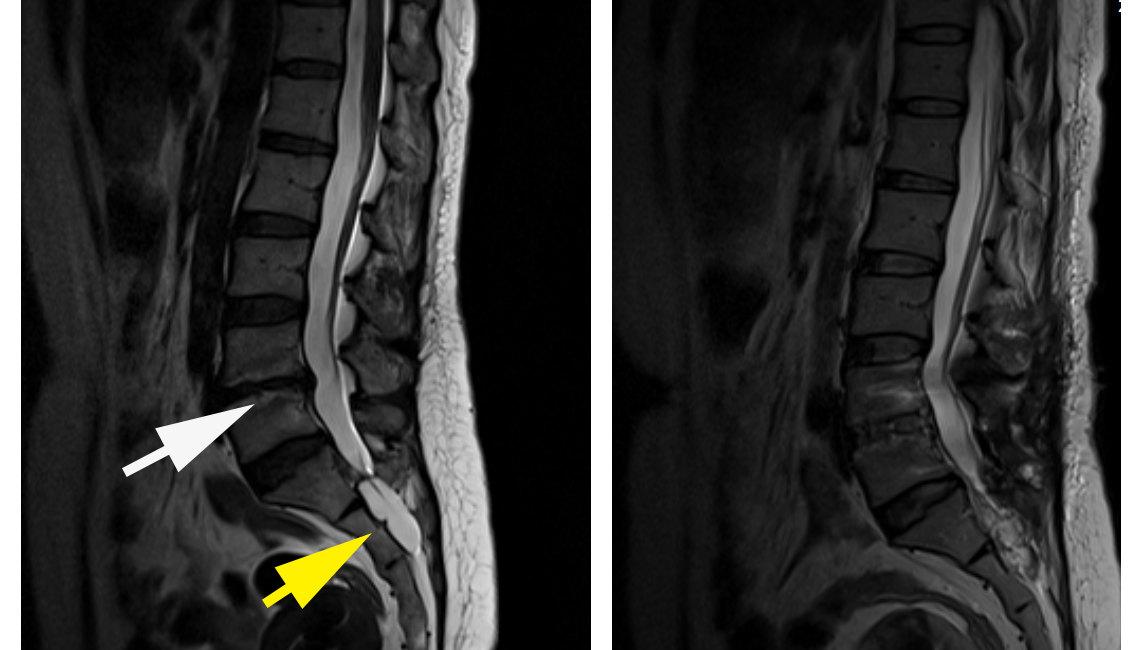

正确认识和治疗骶管囊肿

骶管囊肿实际上是一种脑脊液漏,不是罕见病,而是地地道道的常见病,人群发病率达到5%,在腰骶部核磁共振检查时经常发现,其中大概五分之一是有症状的。骶管囊肿属脊膜囊肿的一种类型,大体分为两种:

Nabors IB型:不含有脊神经根纤维的硬膜外脊膜囊肿(Nabors IB型),为先天性硬膜憩室或先天性硬膜缺陷所致蛛网膜疝出,多位于骶管S1-3水平,常见于成年人,男女之间无明显差异。

Nabors II型:含有脊神经根纤维的硬膜外脊膜囊肿,又称之为Tarlov神经束膜囊肿或脊神经根憩室(Nabors II型),为脊髓神经根袖远端的异常扩张形成囊肿,一般位于S2-3水平脊神经节或其远端,多见于成年人。